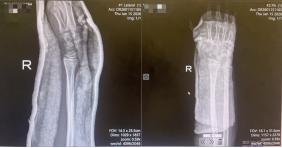

1月15日,9岁男童小洋因不慎摔伤致右腕部剧烈疼痛、活动受限4小时,被紧急送往西安市红会医院就诊。经影像学检查,确诊为右桡骨远端骨折合并骨骺滑脱,骨折类型复杂,复位难度较高。

患儿入院时携带的X线片显示,右桡骨远端骨皮质连续性中断,骨折端成角畸形,并伴有骨骺滑脱。此类涉及骨骺的儿童骨折对复位精度要求极高,既要恢复骨骼的正常解剖对位,以保障肢体功能及骨骼正常发育,又需最大限度避免对骨骺造成二次损伤,以免影响未来的骨骼生长,这给治疗带来了不小的挑战。